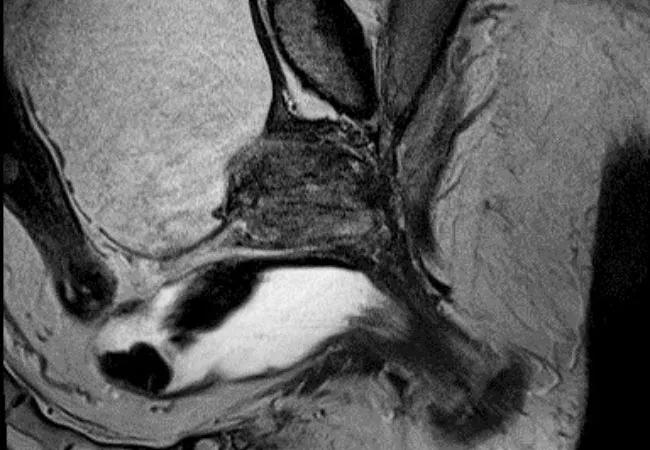

Brachytherapy for prostate cancer is one approach at Cleveland Clinic for patients with localized prostate cancer. Jay Ciezki, MD, radiation oncologist in Cleveland Clinic’s Glickman Urological & Kidney Institute, hopes widespread adoption of the modality is on the horizon.